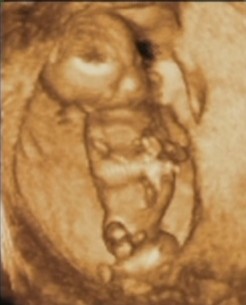

A suliban minden jól ment, hétfőn sikeresen levizsgáztam matekból:4-re. Fogorvosnál minden ok, a gyermek fél éves korában kell újra jelentkeznem. A leányzót kb. 2800 grammra becsülték a héten, a méretei alaján.

Minden mérete kisebb volt, mint a kora, de az orvosom és a szonoráfus sem vélte rossznak a leletet. Úgy döntöttem, én sem parázok rajta, majd megnől idekint a gyerek.